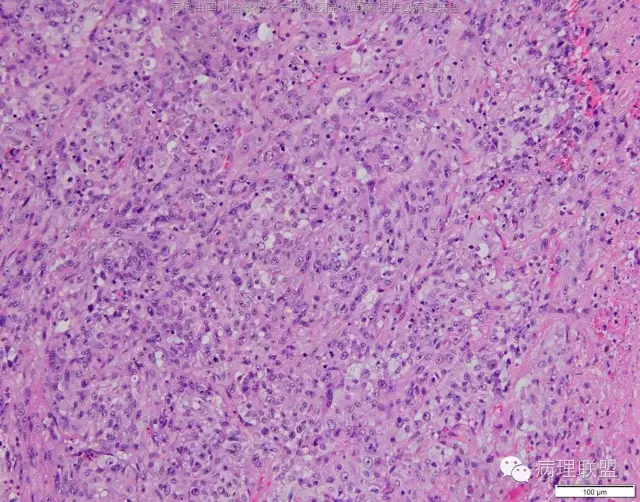

M/47 肺部占位,大小2*1*0.6cm(病例由四川攀枝花市中心医院 沈国菊提供,致谢!)

@张丽 免疫组化腺癌,鳞癌,神经内分泌,恶黑标记均为阴性,只有广谱CK跟Vimentin阳性,准备发大细胞癌

@沈国菊 肺大细胞癌的签发有时是个排他性诊断,我的体会:大细胞的标准:按淋巴细胞直径3倍来算,需要大于这个值,不能等于(从图给出,符合)。神经内分泌的标记(CD56 SYN CgA)完全阴性的可能性不是没有,建议重做试试;细胞的异型性大(符合);Ki67的指数高,应该非常高(您这里没有给出)。这仅仅是我个人体会,我说的不一定正确。

感谢您的精彩病例,采图非常漂亮,并且有标尺(特别赞)。魏老师,Ki-67阳性大于90%,送检7组淋巴结6/7见肿瘤转移。